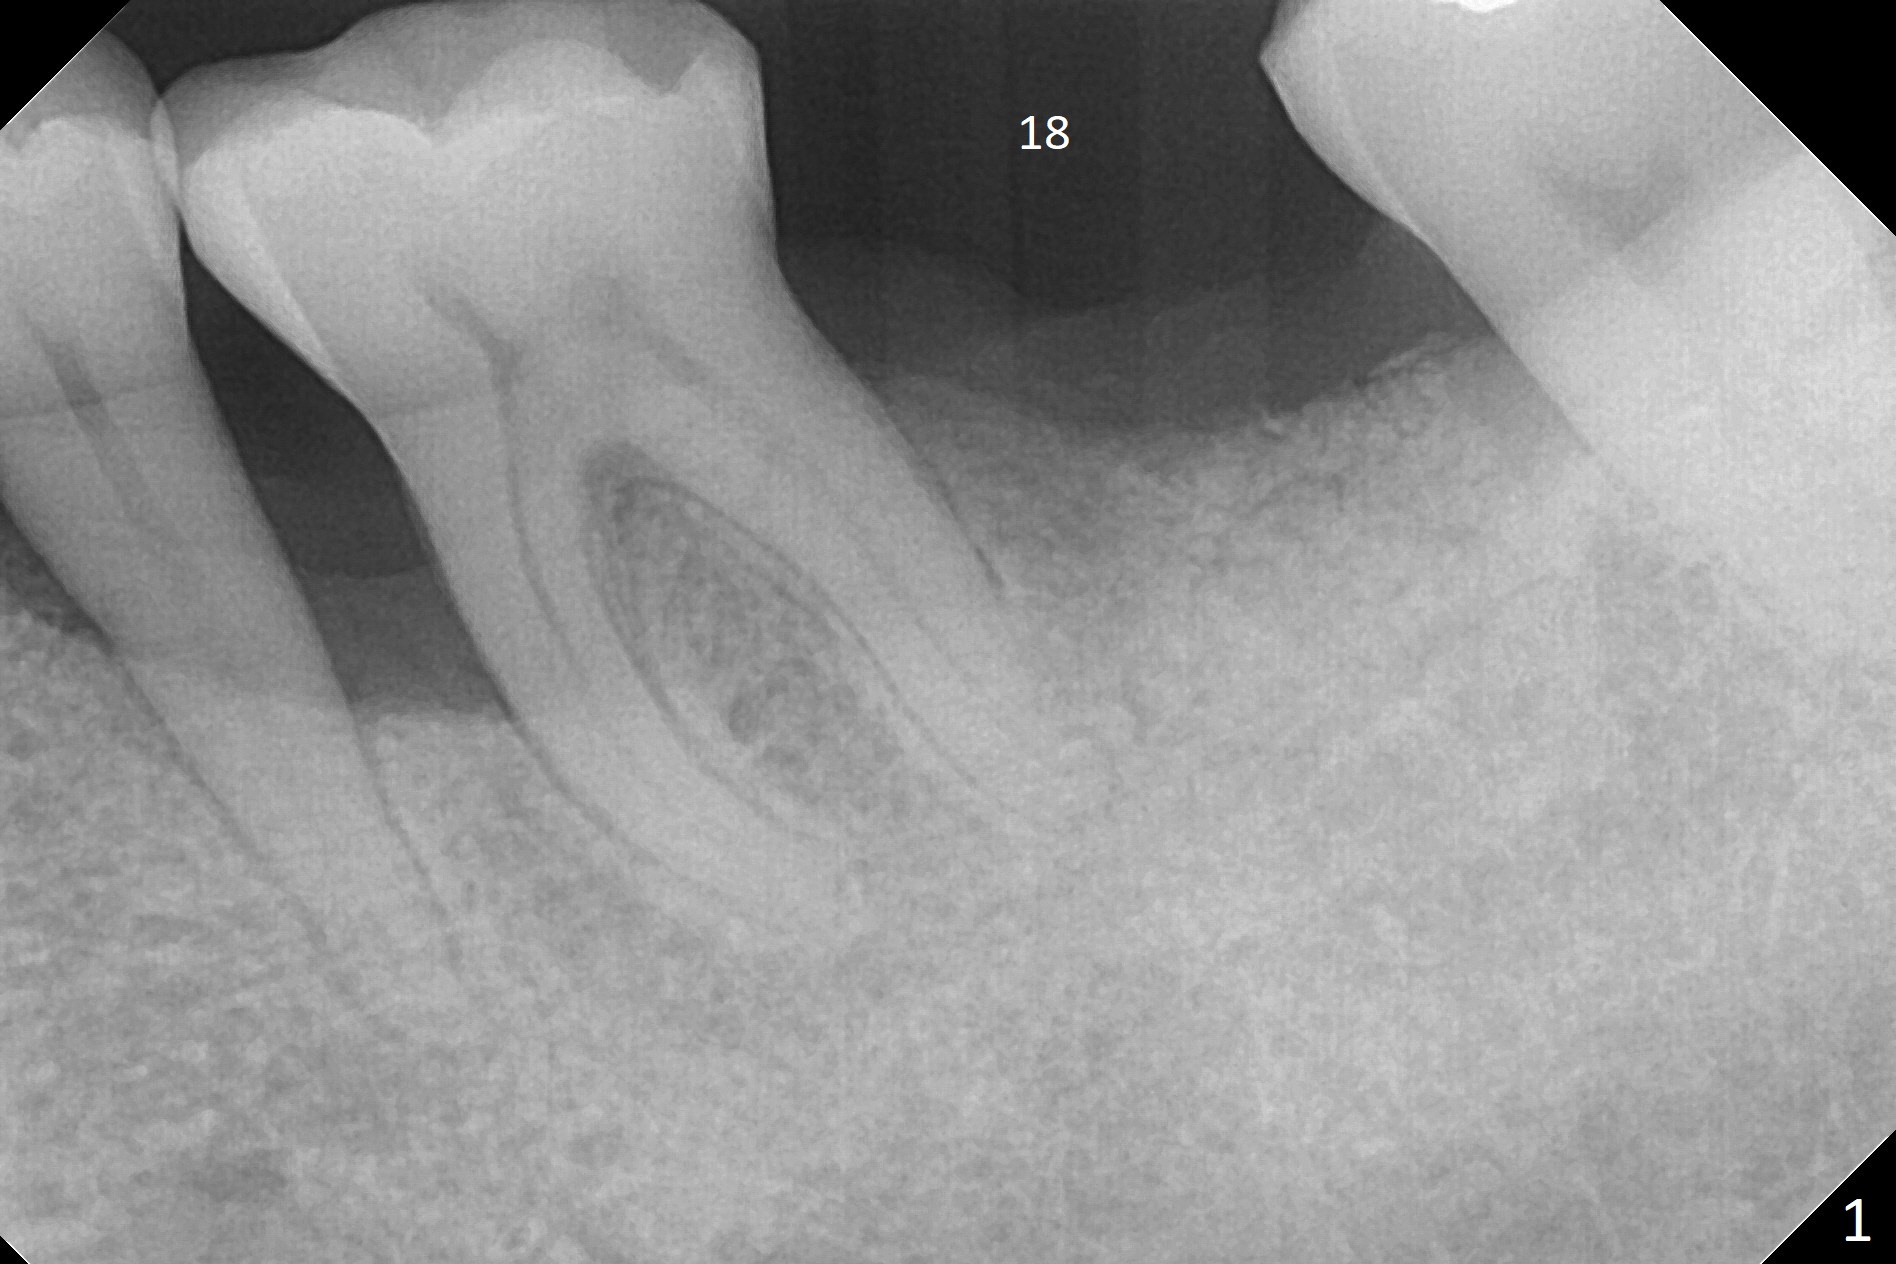

A 49-year-old man returns for #14 and 15 implant impression. The tooth #18 is buccally shifted with mobility, which is incompatible with #14 and 15 restoration. The tooth has to be extracted with socket preservation (Fig.1). A piece of 6-month collagen membrane is used to cover allograft. The socket is healing 9 days postop (Fig.2), probably related to its small wound. Three months and a half postop (Fig.3), CT shows bone healing (Fig.4 sagittal (thin) section, 5 (thick section); 6 (coronal (thin) section). A 5x8.5 mm implant will be placed (Fig.7,8).